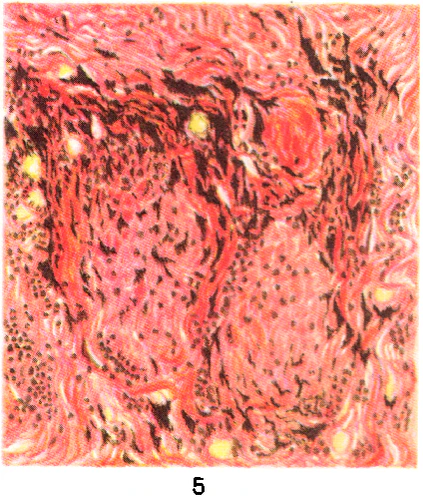

При бериллиозе морфологические изменения характеризуются диффузным поражением обоих лёгких и плевры, распространённым гранулёматозом и хроническим межуточным (синоним «промежуточный») пролиферативным процессом, локализующимся в перегородках альвеол, под плеврой, перибронхиально, периваскулярно. Гранулёмы — серовато-белого цвета, плотной консистенции, размером от 0,2 до 1,5 см. Гранулёма состоит в основном из гистиоцитов, эпителиоидных клеток с примесью (главным образом по периферии) лимфоидных, плазматических и гигантских клеток типа клеток инородных тел (цветн. рис. 4—9). Гигантские клетки содержат кристаллические образования. В дальнейшем происходит созревание клеток гранулёмы с появлением в ней фибробластов. Фибробласты начинают продуцировать коллагеновые волокна, и процесс завершается развитием на месте гранулёмы соединительнотканного узелка, который нередко подвергается гиалинозу. В гранулёмах обнаруживают типичные для Б. конхоидальные (раковинообразные) тельца диаметром от 2,5 до 10 мкм, которые могут образовывать скопления диаметром до 190 мкм. Иногда они располагаются в многоядерных гигантских клетках. Конхоидальные тельца окрашиваются гематоксилином в синий, сине-фиолетовый цвет, иногда дают положительную реакцию на железо, имеют вид флюоресцирующих голубоватых зёрен при освещении ультрафиолетовыми лучами. Наряду с гранулёматозом в межальвеолярных перегородках наблюдается диффузный пролиферативный процесс с наличием гистиоцитов, лимфоидных, плазматических клеток, фибробластов, заканчивающийся диффузным пневмосклерозом. Наблюдается бронхит, возможно развитие бронхоэктазов. Встречаются участки ателектаза и эмфиземы. В кровеносных сосудах могут иметь место эндартериит, эндофлебит, тромбозы. Описанные изменения в лёгких обычно приводят к развитию лёгочного сердца[6].